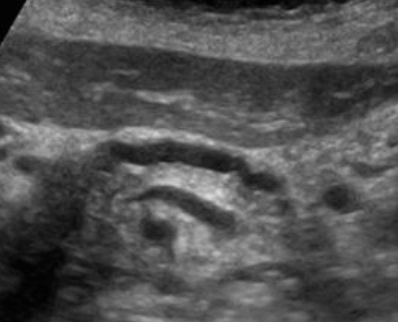

US finding

- 담낭관 또는 담낭 경부에 결석이 확인된다.

- 총간관(CHD) 또는 담낭관(cystic duct)의 확장소견이 보인다.

- 간내외 담관의 확장이 관찰된다.